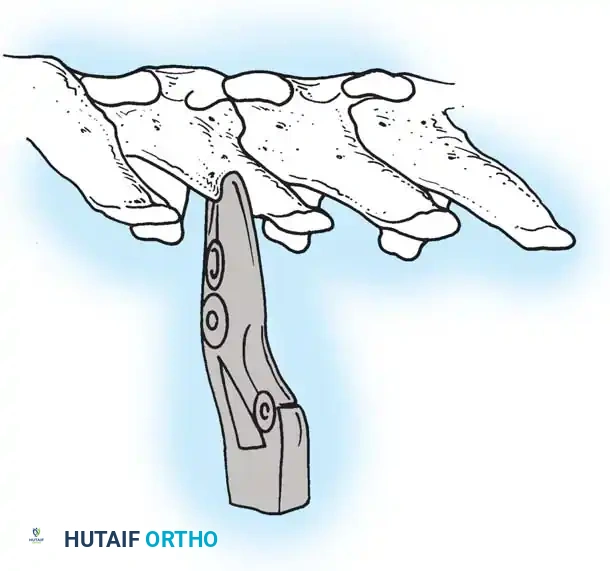

The Moe Technique (Lumbar Spine)

In the lumbar spine, the facet joints are oriented in a more sagittal plane, necessitating a modified approach.

Fig. 38-27: The Moe technique adapted for lumbar facet fusion, addressing the sagittal orientation of the joints.

- Utilize a small osteotome or a needle-nose rongeur to resect the adjoining joint surfaces.

- This creates a distinct rectangular defect within the sagittally oriented joint space.

- Pack this defect forcefully with cancellous bone graft.

- Proceed to decorticate the entire exposed posterior elements (laminae and transverse processes) using Cobb gouges, always directing force away from the spinal canal.